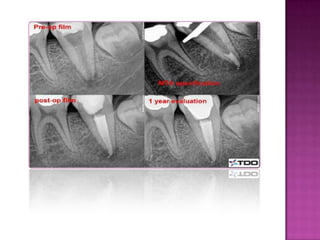

The document discusses pulp therapy for primary and permanent teeth. Pulp therapy is divided into vital pulp therapy and non-vital pulp therapy. Vital pulp therapy is used for primary teeth with normal pulps or reversible pulpitis, and involves procedures like pulpotomy to maintain the vitality of the remaining pulp. Non-vital pulp therapy is used for primary teeth with irreversible pulpitis or necrotic pulps, and involves procedures like pulpectomy to remove the entire pulp. Maintaining primary teeth has benefits such as preventing malocclusion, aiding mastication, and preserving space for permanent teeth.